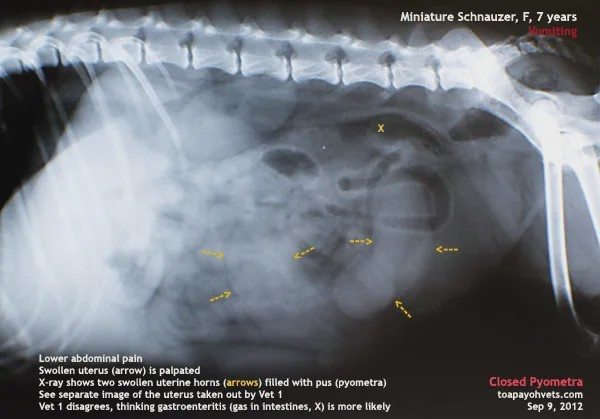

一般情况下,发现阴门流脓、同时狗狗未做绝育,就可以确诊。此时如果进行腹部B超,可以看到明显的子宫内膜增厚、子宫内有一定数量的暗区。 闭锁性子宫蓄脓就要危险许多。因为子宫闭锁,狗狗患病前期不会出现特别的生病征兆,导致家长很难发现狗狗已经病了。等到发觉狗狗异常的时候,病情往往比较危急。

这时的狗狗可能表现出肚子腹围增大、消瘦、多饮多尿、食欲不振等。通过腹部超声和血常规检查可以得出准确答案。如果过度延误,狗狗的子宫有可能破溃,导致细菌性的脓汁流入腹腔,形成腹膜炎。